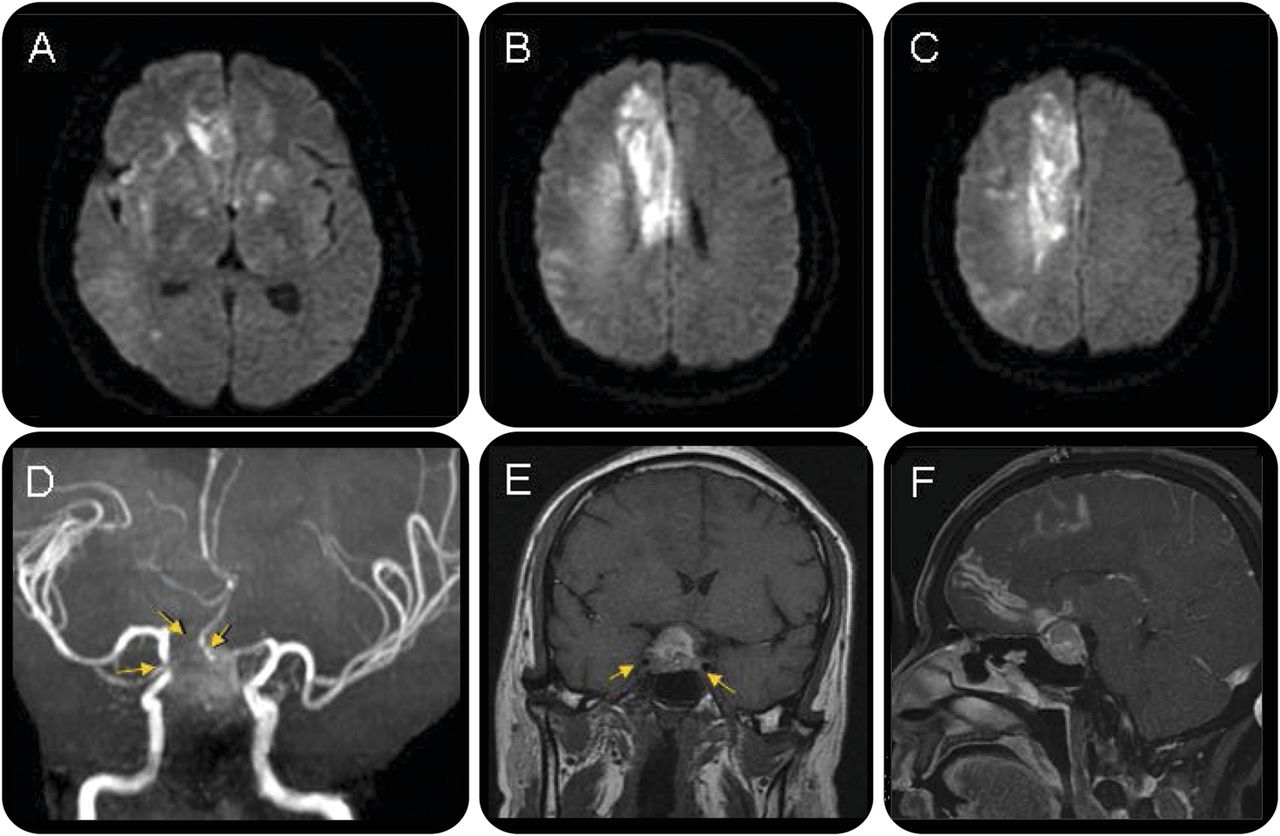

另一个大脑MRI表现,diffusion-weighted成像(驾车)显示高信号符合地区由两个大脑前动脉(留住)和右大脑中动脉(MCA) (图2中,得了)。领域的高信号对醉酒驾车小于CT扫描射线透射性,这表明,部分病变出现在最初的CT的血管性水肿及而非脑梗塞。垂体macroadenoma被发现包含右颈内动脉(ICA)海绵窦。其isointensity最初的T1加权图像相比,垂体腺瘤部分打开hyperintense T1和t2加权图像,表明肿瘤内出血(图2中,E和F)。颅磁共振血管造影术披露严重狭窄的远端对ICA和贫穷的可视化都留住,符合急性大规模脑梗死的诊断的领土留住和右大脑中动脉(图2 d)。在没有传统的血管危险因素的情况下,病人的梗塞是由垂体卒中与ICA压缩。

Diffusion-weighted图像揭示限制扩散双边大脑前动脉(ACA)和右大脑中动脉领土(a - c)。磁共振血管造影显示严重狭窄的远端颈内动脉(ICA)和穷人的可视化留住(D,箭头)。垂体macroadenoma部分hyperintense在t1影像(E),表明肿瘤内出血,增强的脑下垂体腺瘤瘤旁表面(F)。扩展到海绵窦导致双边intracavernous ICA的压缩,更糟糕的是在右边(E,箭头)。